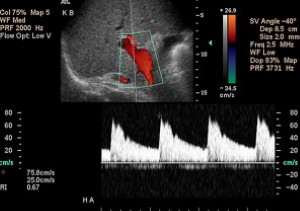

Phần ngoài gan, động mạch gan riêng đi trước tĩnh mạch cửa ở cửa gan, rồi phân các nhánh trong gan theo các tĩnh mạch cửa. Mặc dù chỉ cung cấp 20% đến 30% lưu lượng máu đến nhu mô gan, động mạch gan là nguồn cung cấp máu chủ yếu tới đường mật. Động mạch gan bình thường có sóng động mạch sức cản thấp với dòng chảy tâm trương liên tục (Hình 3). Trong tình trạng nhịn ăn, các số đo tốc độ tâm thu bình thường khoảng 30 tới 40 cm/s, tốc độ tâm trương 10 tới 15 cm/s [2]. Số đo Doppler của chỉ số kháng (RI) trong động mạch gan ở người bình thường nhịn ăn thay đổi từ 0,55 tới 0,81 (trung bình 0,62-0,74) [2].

Hình 3. Động mạch gan bình thường ở bệnh nhân nam 48 tuổi mắc viêm gan C. Ảnh siêu âm duplex Doppler và màu ở cửa gan cho thấy phổ sức kháng thấp của động mạch gan.